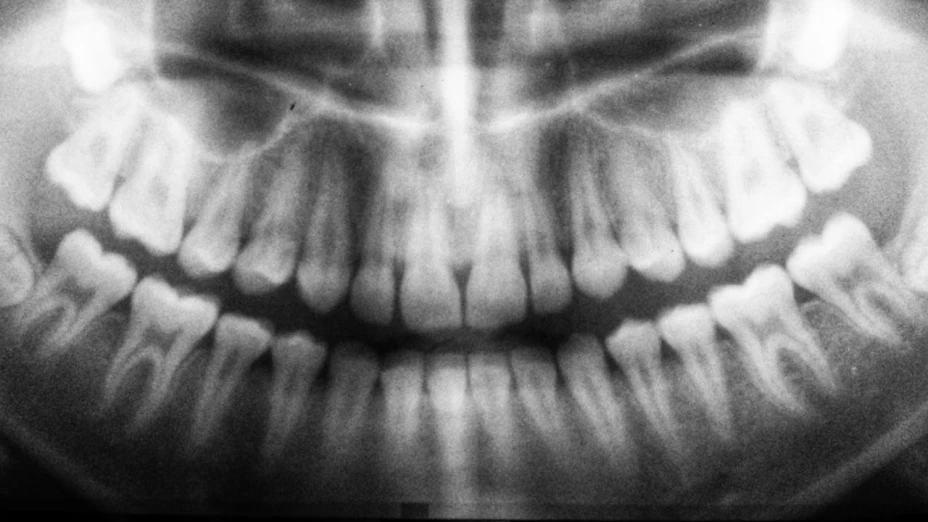

En España, una niña de 6 años acudió a una clínica dental privada en Alzira, Valencia, para que le trataran algunas caries y le extrajeran un diente de leche que estaba por caerse.

Niña de 6 años muere por un diente de leche